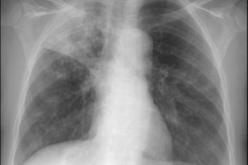

الفقر هو سبب إنتشار مرض السل ويصيب الأطفال لعدم تلقيحهم بلقاح" BCG" أثناء الولادة أرجع البروفيسور نافتي سليم، رئيس مصلحة الأمراض الصدرية والسل بالمستشفى الجامعي مصطفى باشا "ليون بارنار"، أسباب انتشار … 08 فيفري